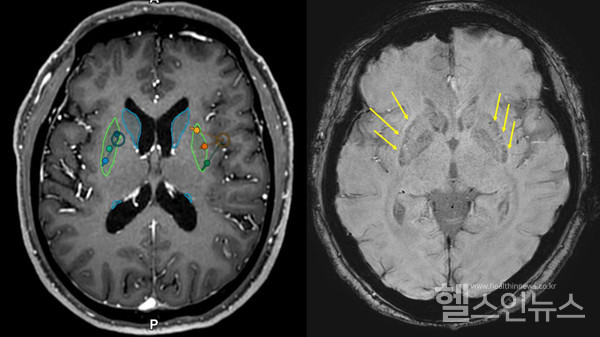

이번 이식은 식품의약품안전처 승인을 받아 세브란스병원 신경외과(연구책임자 장진우 교수)와 신경과(이필휴 교수)가 협업해 진행했다. 이식한 임상시험용 의약품은 인간 배아줄기세포에서 분화시킨 중뇌 도파민 신경전구세포다.

대상은 파킨슨 진단 5년 이상 지났으며 약물 치료를 받았지만 효과가 떨어지거나 이상운동증 등 부작용을 보인 환자다.